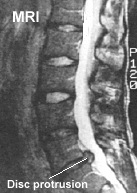

자기 공명 영상 촬영 (MRI)

최근 허리 디스크의 진단에 가장 보편적이고 정확한 방법으로 사용되고 있는 검사법입니다. 척추체, 디스크, 주위 연부조직까지 자세하게 볼 수 있으며 횡단면 뿐만 아니라 종단면까지도 촬영할 수 있어 CT보다 많은 정보를 얻을 수 있고 디스크 자체의 변성 여부도 알 수 있습니다.